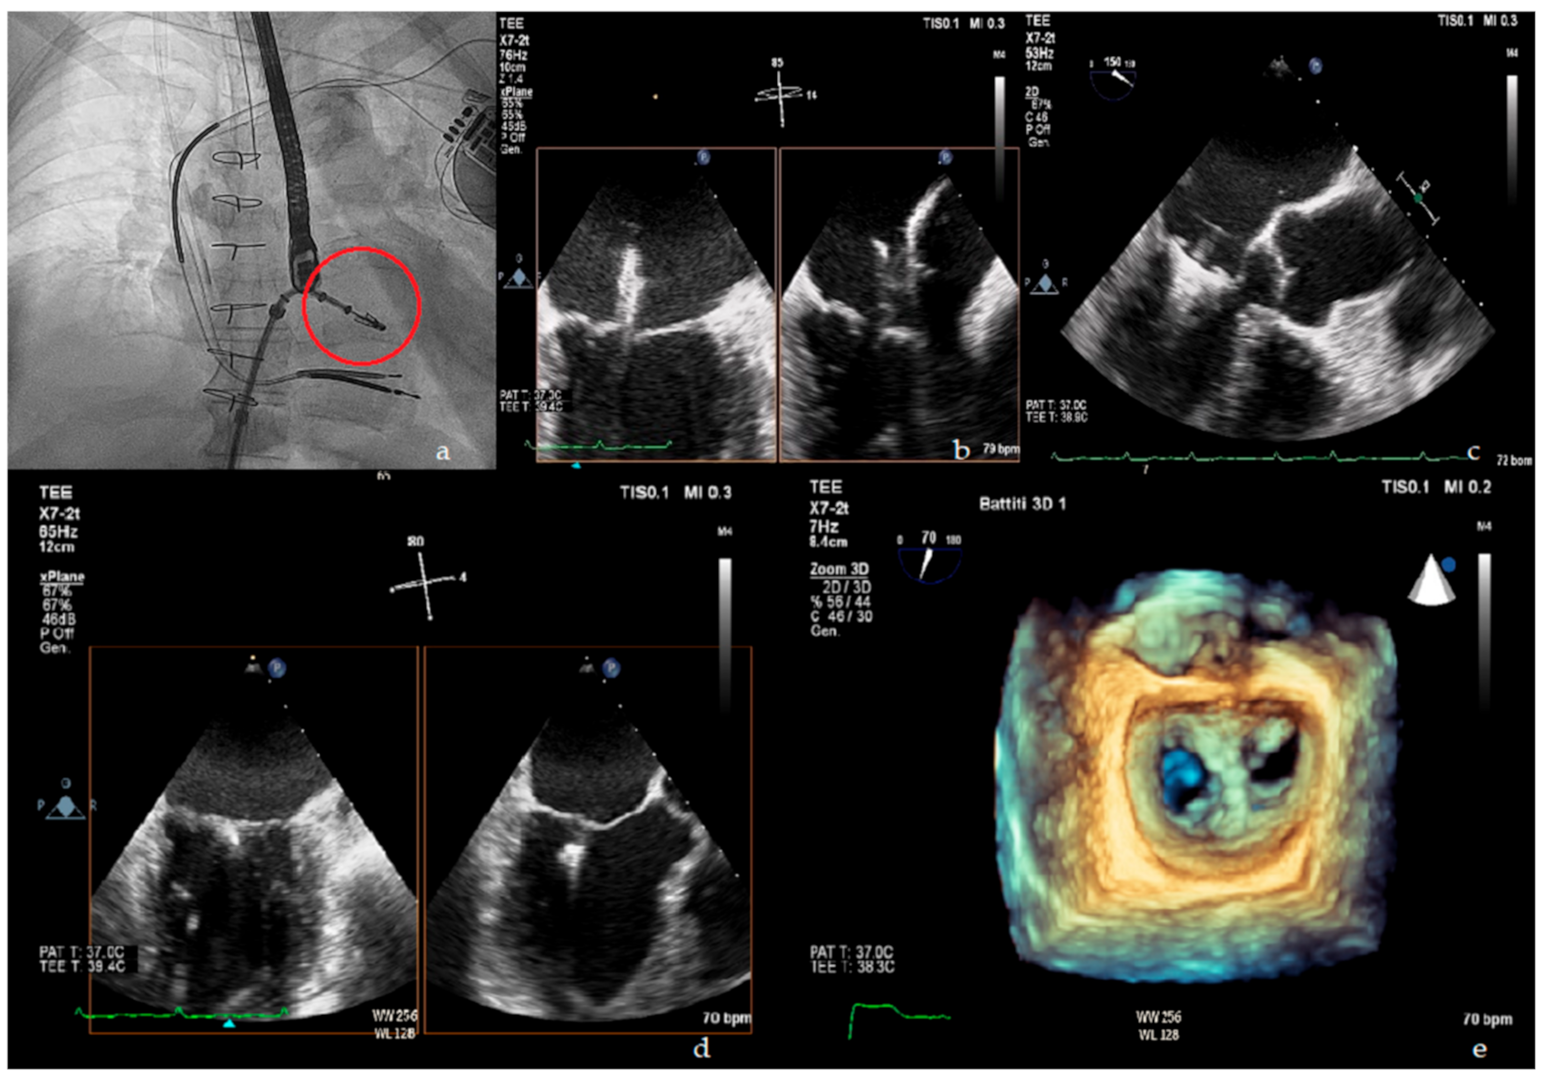

The MitraClip procedure is performed in the catheterization laboratory using echocardiographic and fluoroscopic guidance (Figure 1). The patient is under general anesthesia and systemic anticoagulation with an activated clotting time (ACT) target > 250 s administered. The MitraClip itself is a cobalt chromium clip covered with a polypropylene fabric whose function is to grasp and approximate two opposite segments of the anterior and posterior leaflet. The clip is delivered percutaneously through a venous femoral access. Transseptal puncture is performed in order to introduce the clip delivery system into the left atrium and then into the left ventricle. Once in the left ventricle, the delivery system is steered and aligned over the origin of the regurgitant jet, and leaflet grasping is performed. In its most recent version, the MitraClip system allows for independent leaflets grasping. Once adequate grasping is obtained, desired position of the clip is confirmed and functional assessment of the mitral valve is done, the clip can be released from the delivery system or reopened and repositioned. Residual MR can be targeted by positioning additional clips [32]. Procedural success is defined as proper placement of the device without procedural mortality and with reduction in post-procedural MR by ≥1 grade from baseline and to an absolute level of ≤moderate MR.

Figure 1.

Upper panel: (a) fluoroscopic view of MitraClip delivery system (red circle); (b) X plane transoesophageal echocardiogram (TOE) view of MitraClip in left atrium; (c) TOE left ventricle outflow tract (LVOT) view of MitraClip positioning. Lower panel: (d) X plane TOE view of final clip release; (e) 3D en face view showing the double orifice shape of the mitral valve after clip implantation.